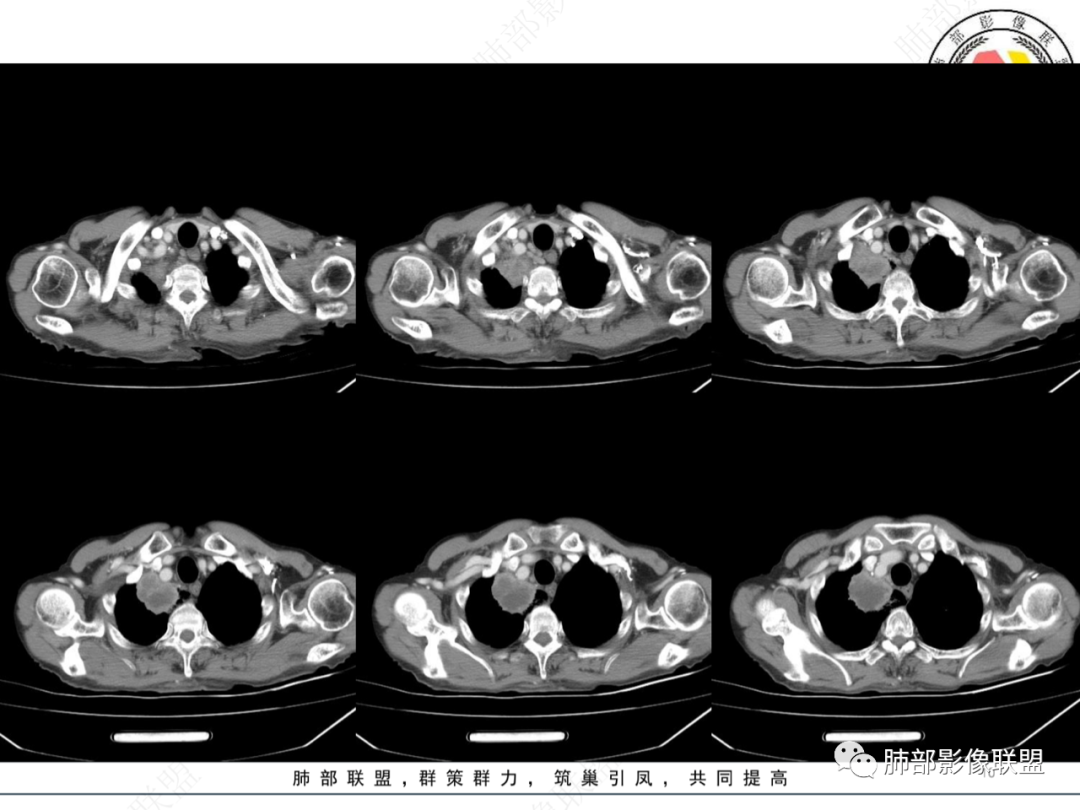

最让人忐忑的:淋巴结

炎性:结核多见,肿瘤:鳞癌多见

最让人放心不下的是这里

南边  :

上腔静脉外面按理没有淋巴结啊

其次:团块影的壁:厚薄不均匀

从上面的图看:炎性肯定有

癌?结核?不能排除